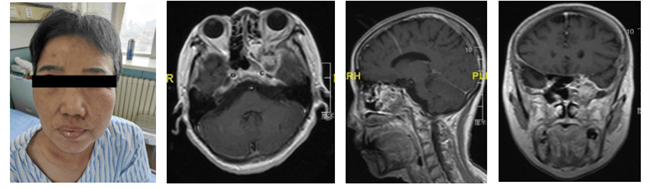

【手术|哈医大一院完成内镜下复杂颅内外沟通病变手术】在王宁教授的带领下 , 邵奇主治医师 , 房宇龙住院医生协助患者顺利完成了术前相关检查及会诊 , 确诊为颅内外沟通型占位性病变 , 为患者找到了真正的病因 。

文章图片

患者术前相关检查结果 。 哈医大一院 供图